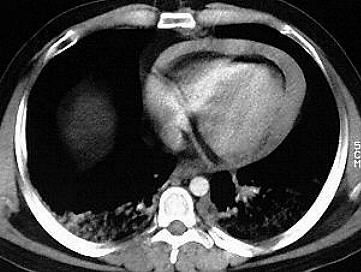

Perikarderguss

Akut auftretende perikardiale Flüssigkeitsansammlungen können ab ca. 250 ml zu einer Herzbeuteltamponade führen. Als Ursachen dafür kommen beispielsweise Aortendissektionen, perforierende Traumen, Urämie sowie bakterielle, virale und rheumatoide Perikardentzündungen in Frage. Computertomographisch lässt sich ein zirkulärer, dem subepikardialen Fettgewebe anliegender hypodenser Saum darstellen. Bei einer zugrunde liegenden Perikarditis können verdickte, kontrastmittelaufnehmende Perikardblätter nachweisbar sein.